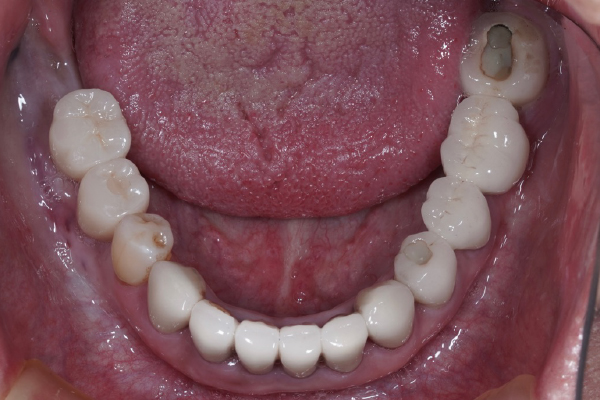

【お悩み】

奥歯を失ってから、食事の際にしっかり噛めず不便を感じていました。入れ歯には抵抗があり、インプラントを検討して来院されました。

【診断】

歯科用CT検査により、インプラントに必要な骨量が十分にあることを確認しました。

【治療内容】

骨造成は行わず、患者さまの状態に合わせたインプラント治療を行いました。

【治療後】

治療後は奥歯でしっかり噛めるようになり、食事のストレスがなくなったとお話しされています。

【この症例のポイント】

一般的な奥歯の欠損であれば、状態によっては比較的シンプルな治療計画でインプラントが可能なケースもあります。